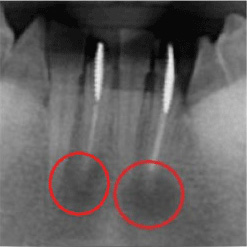

一見簡単な処置のように思えますが、「根管を綺麗に清掃する作業」は非常に困難を極めます。なぜなら、根管は非常に複雑に入り組んでおり、しっかりと清掃を行わなければ、「痛み」「腫れ」などの原因となり、「根尖病巣」という病気にもなるためです。下の画像ですが、「黒い部分」が神経の入っている管であり、この部分をしっかりと綺麗に清掃する必要があります。

当院で処置した症例をご紹介します。

他院で抜歯と言われてしまった歯でも抜歯せずに対処した症例も多数あります。

黒い影が出ている部分が問題の個所で(根尖病巣)、治療後はこの影がなくなっているのが見て取れると思います。

保険適用。根尖病巣を治療した症例。リスクとして、稀ではありますが再発することがあります。